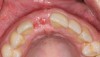

A 33-year-old woman presented with a buccal fistula at the apex of No. 8, and there was an 8-mm mid-buccal probing depth (Figure 1). The tooth had been treated multiple times by an endodontist. Based on the tooth's dental history, mobility, and its poor endodontic and periodontal prognosis, it was deemed hopeless and scheduled for extraction (Figure 2).

Fig 1. Fistulous tract at apex of tooth No. 8 (arrow).

Figure 1